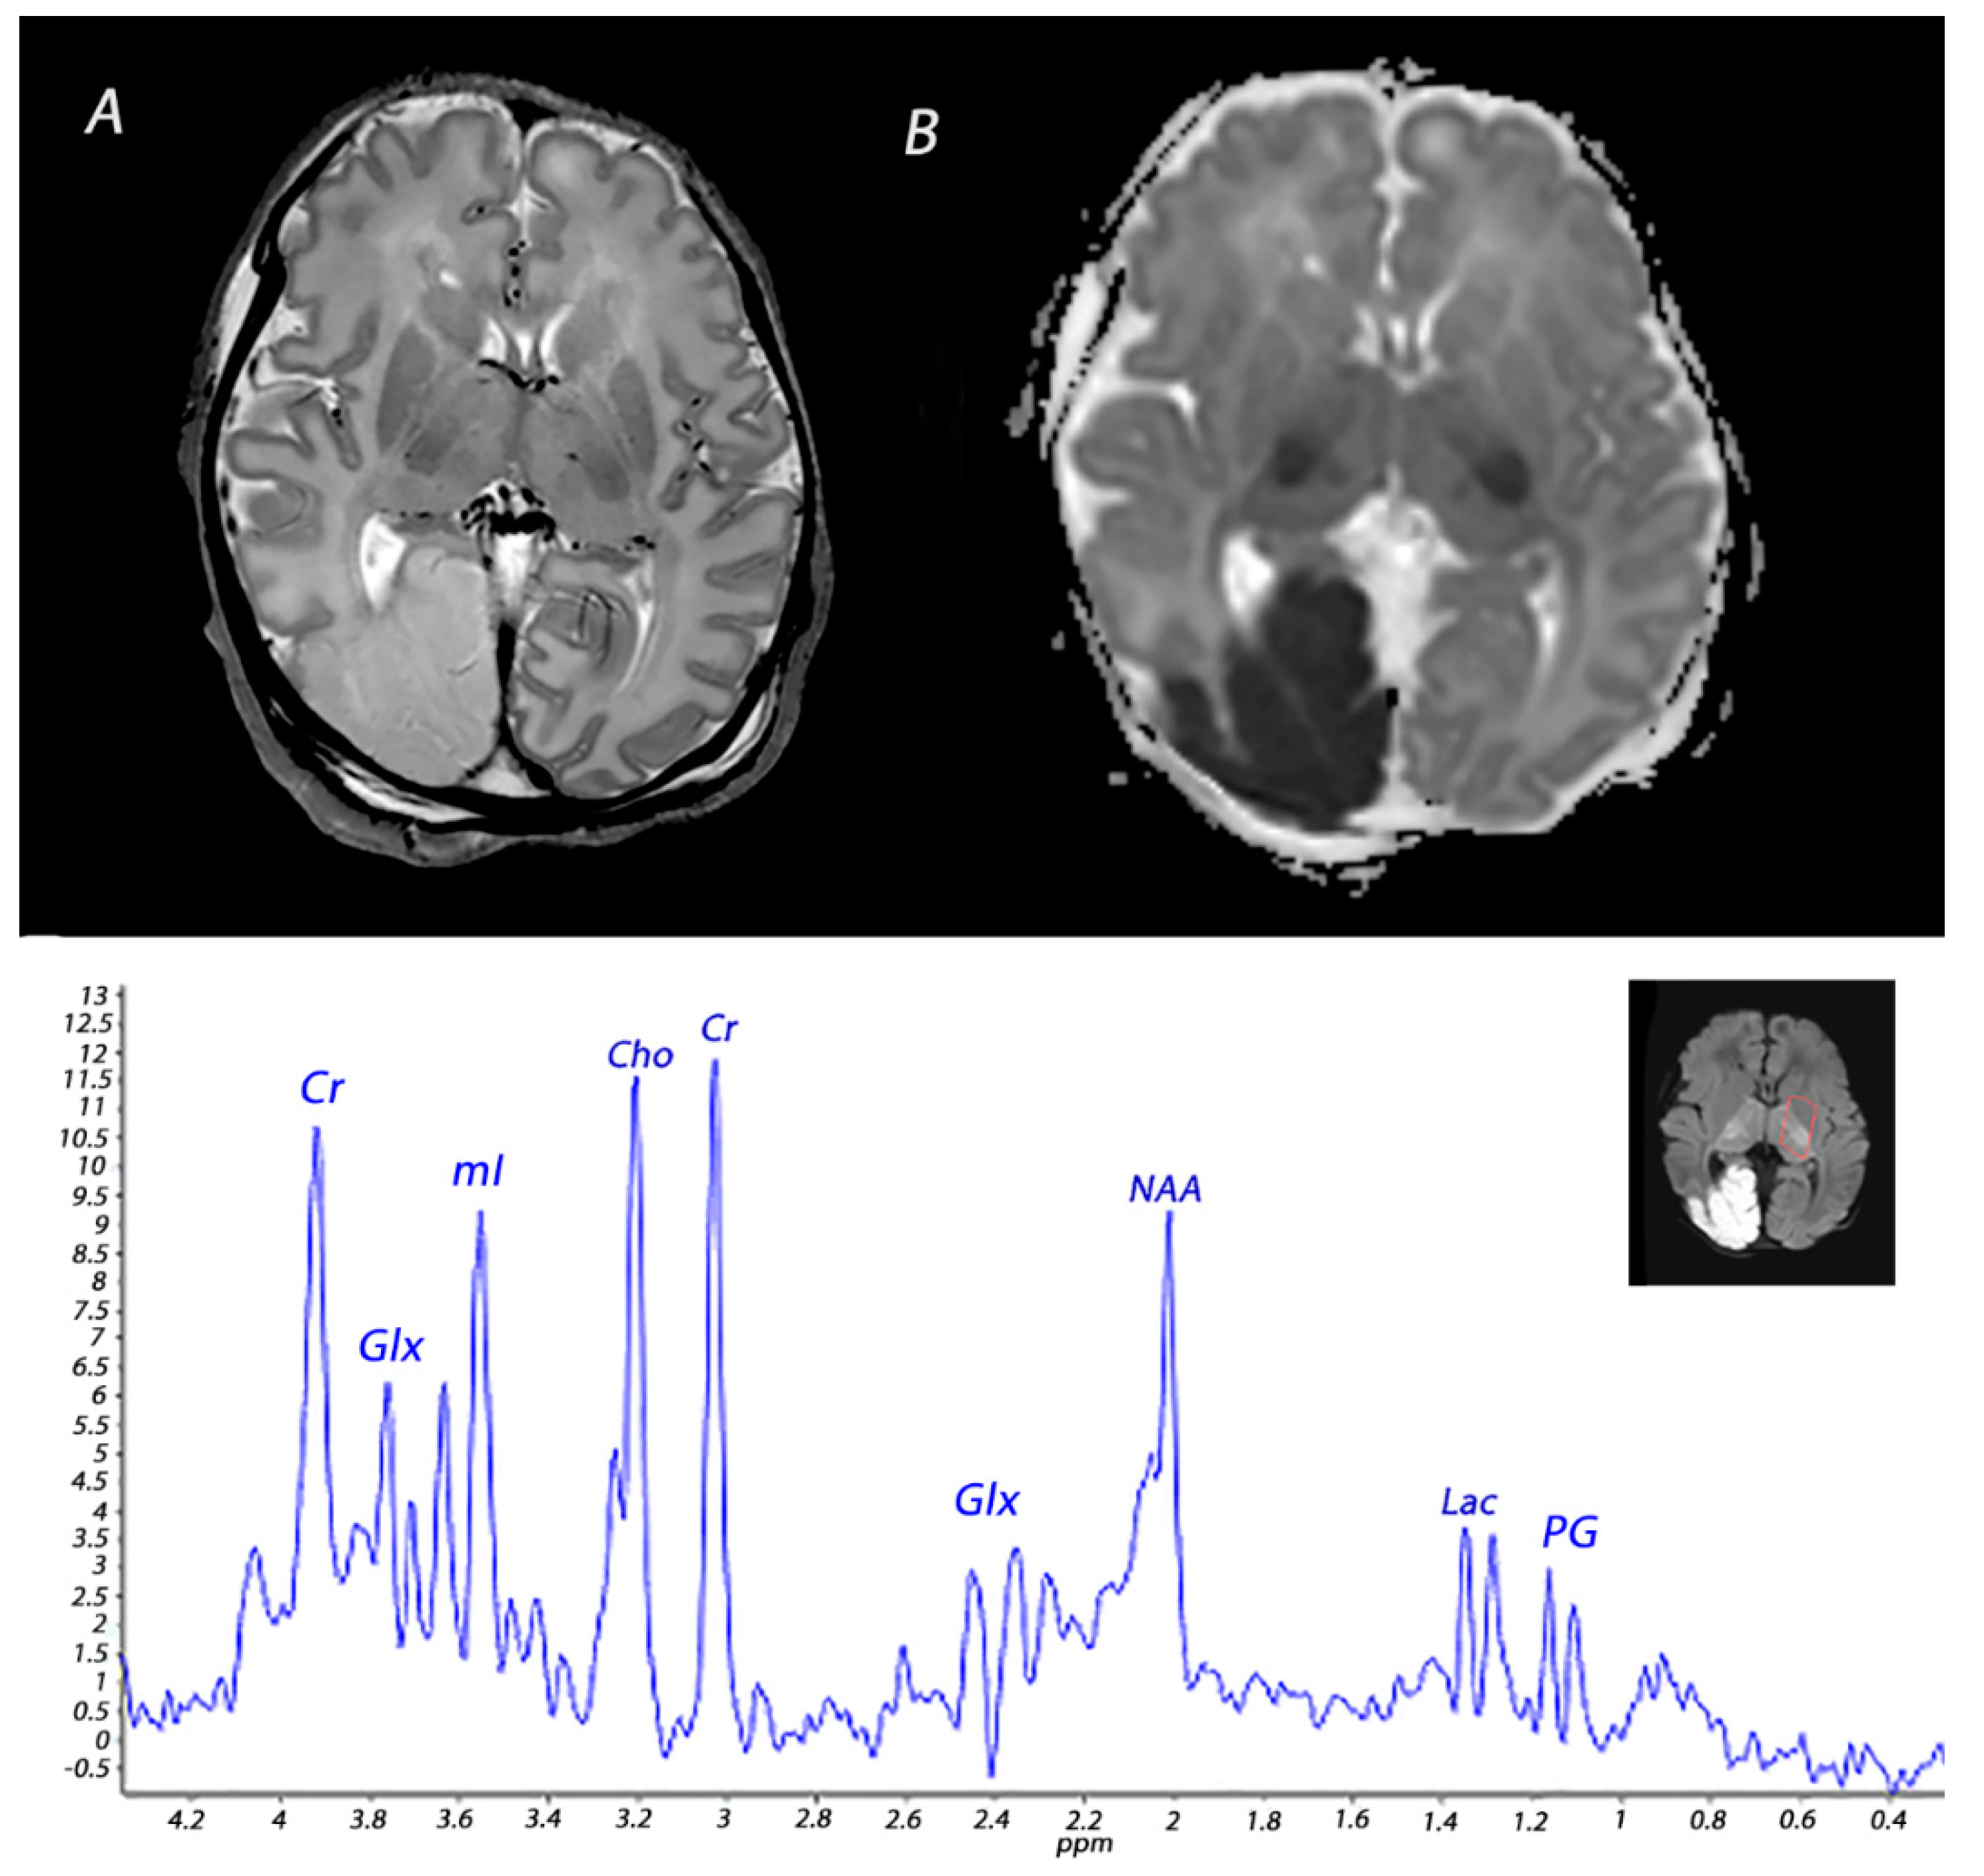

5. Magnetic Resonance Spectroscopy

| 1H-MRS | Increased lactate and decreased NAA in the affected white matter. | Lactate in general increases <24 h and subsequently normalizes by the end of the first week, but persistent elevation has been reported. 1 NAA declines <24 h and remains low during the first 2 weeks after the insult, although some studies have reported that NAA levels do not significantly diminish until approximately 48 h after the insult. 2 | |

| 1H-MRS | Increased lactate and decreased NAA in basal ganglia and thalami. | Lactate in general increases <24 h and subsequently normalizes by the end of the first week, but persistent elevation has been reported. 1 NAA declines <24 h and remains low during the first 2 weeks after the insult, although some studies have reported that NAA levels do not significantly diminish until approximately 48 h after the insult. 2 | |